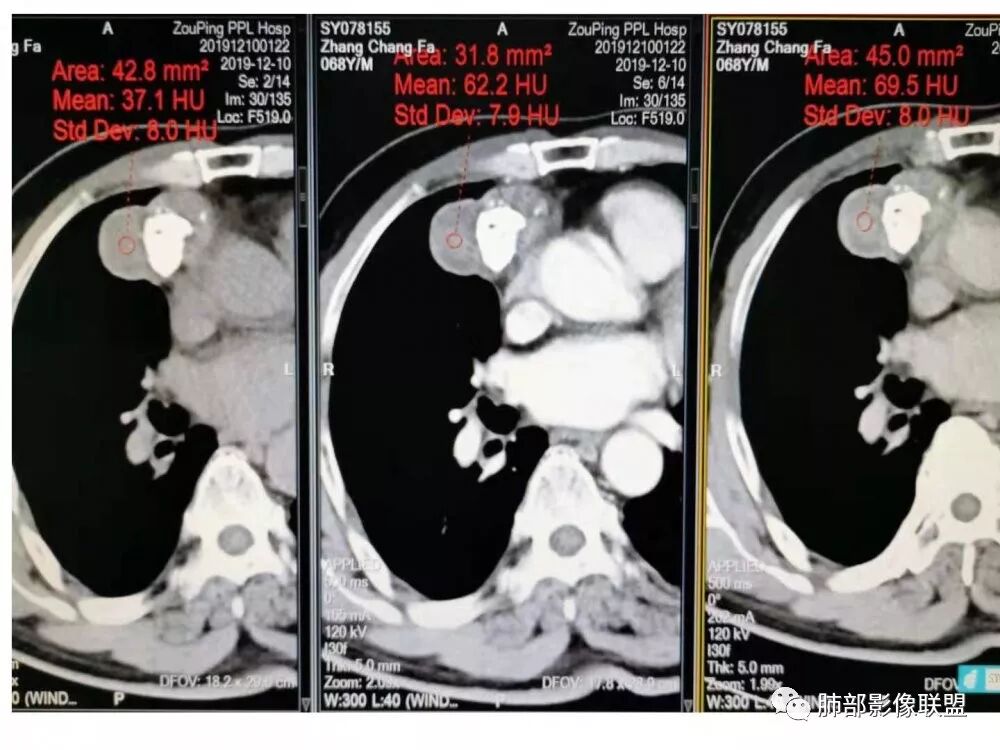

实性部分中度强化——增加20~27HU

1.CD钙化不支持,一般条状短棒状为主,小结节

也有,这么大的钙化少见,分叶也太明显。

2.异位甲状腺:发病率低,强化太弱,一般来说异位甲状腺强化达100多

3.神经鞘瘤:深分叶,这么大钙化罕见